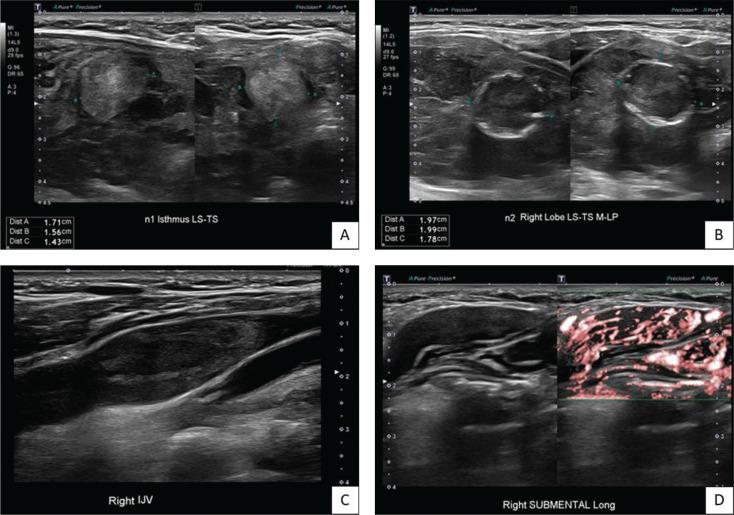

我们报告了一例67岁女性罕见的同步性乳头状甲状腺癌(PTC)和滤泡状甲状腺癌(FTC)的侵袭性病例,该患者最初因格雷夫斯病出现甲状腺毒症。她被发现有两个甲状腺结节,伴有广泛的心脏内肿瘤血栓、有症状的左骨盆骨转移伴病理性骨折、肺转移和纵隔淋巴结转移。进一步检查提示诊断为同步性乳头状和转移性滤泡状甲状腺癌。建议采用根治性手术,随后进行辅助性放射性碘消融治疗,但患者拒绝了所有形式的癌症特异性治疗,仅选择姑息性治疗方法。我们讨论了诊断同步性甲状腺恶性肿瘤时的诊断要点——在本病例中,PTC的明显特征以及由于侵袭性和转移性滤泡病变导致FTC的高可能性。该病例强调了美国放射学会甲状腺影像报告和数据系统(ACR TI-RADS)的潜在局限性,特别是某些提示恶性的超声特征可能未被充分捕捉。值得注意的是,本病例中分化型甲状腺癌的侵袭性表现可能与格雷夫斯病的并存有关,这表明在评估此类患者的潜在甲状腺恶性肿瘤时需要提高警惕。